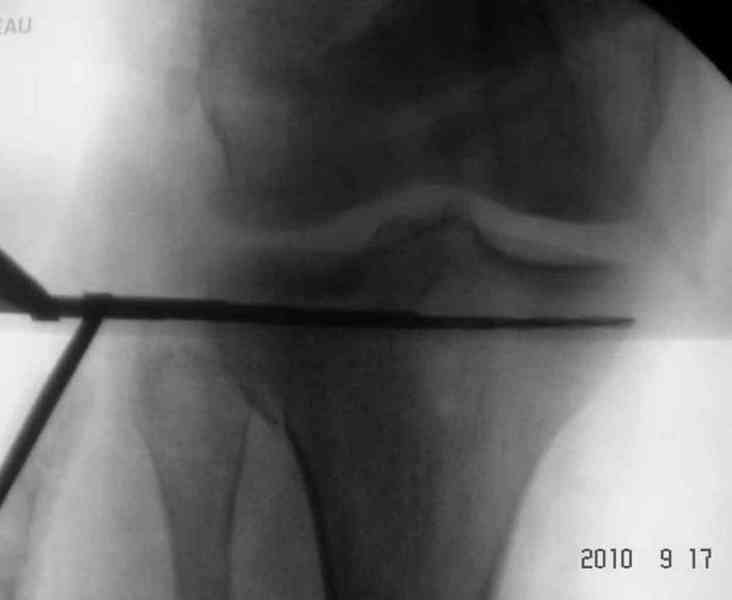

Для внутрисуставных переломов необходимо идеальное сопоставление, а такая задача без КТ срезов усложнится. Только КТ надо делать после дистракции сустава, иначе нельзя получить объективную информацию.

Основная задача в лечении околосуставных переломов является создание солидного базиса в субхондральной зоне. Пластина подпорка (Butress) или субхондральные перкутанные шурупы в виде плота (Raft) для ранних движении.

У больного двухстороннее повреждение, ограничен в нагрузке не менее 8-10 недель. После односторонней фиксации будет активным, хотя бы в пределах койки. Без спешки дождаться улучшения кожных покровов, и аппаратом Илизарова в комбинации с шурупами или спицами, из мини-доступов.